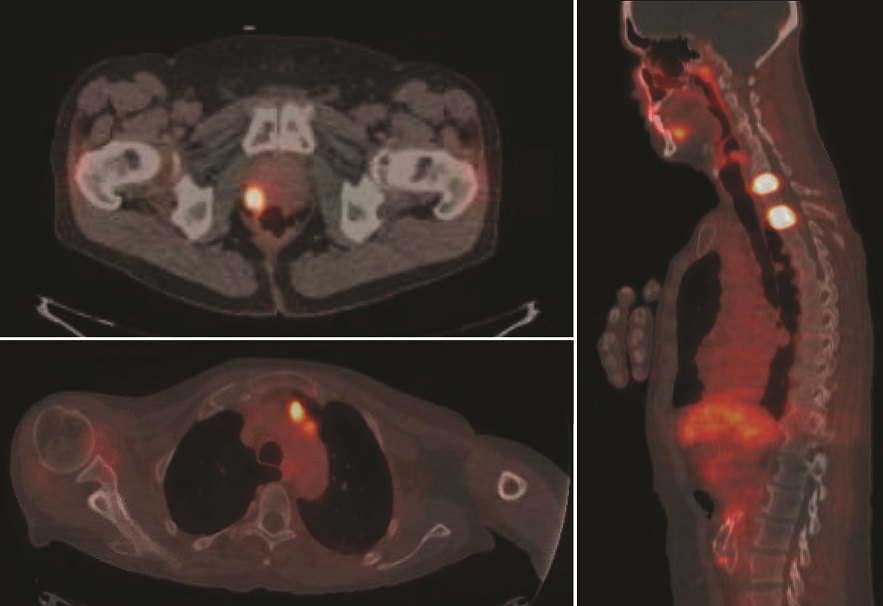

Ridley-Tree’s Nuclear Medicine Department is now

using a radioactive agent called PYLARIFY® (F18-PSMA)

to provide more accurate and earlier detection of prostate

cancer than our previous imaging methods. This diagnostic

tracer, approved by the FDA in May 2021, helps physicians

in two scenarios: 1) when a patient is newly diagnosed

and the physicians want maximum information about the

prostate cancer’s location before treatment, and 2) when a

patient who was previously treated for prostate cancer has

a blood test that suggests cancer has returned.

“Conventional imaging is limited in terms of its ability

to find prostate cancer in the initial staging, and when

determining if the disease has recurred or spread,” explains

William Pace, MD, Nuclear Medicine Physician. “PYLARIFY®

provides us with exceptional clarity and precision that can

find and track the spread of prostate cancer much earlier,

giving our patients

better information when

deciding on a treatment

plan with their doctor.”

F18-PSMA / PET-CT

imaging has greatly

advanced how urologists

and oncologists can

view prostate cancer

metastases and how

they stage the disease. In

patients with an elevated

prostate specific antigen

(PSA), Pylarify® was able

to detect the location of

the recurrent disease in

nearly 2 out of 3 patients,

when the disease was undetectable by prior imaging methods.